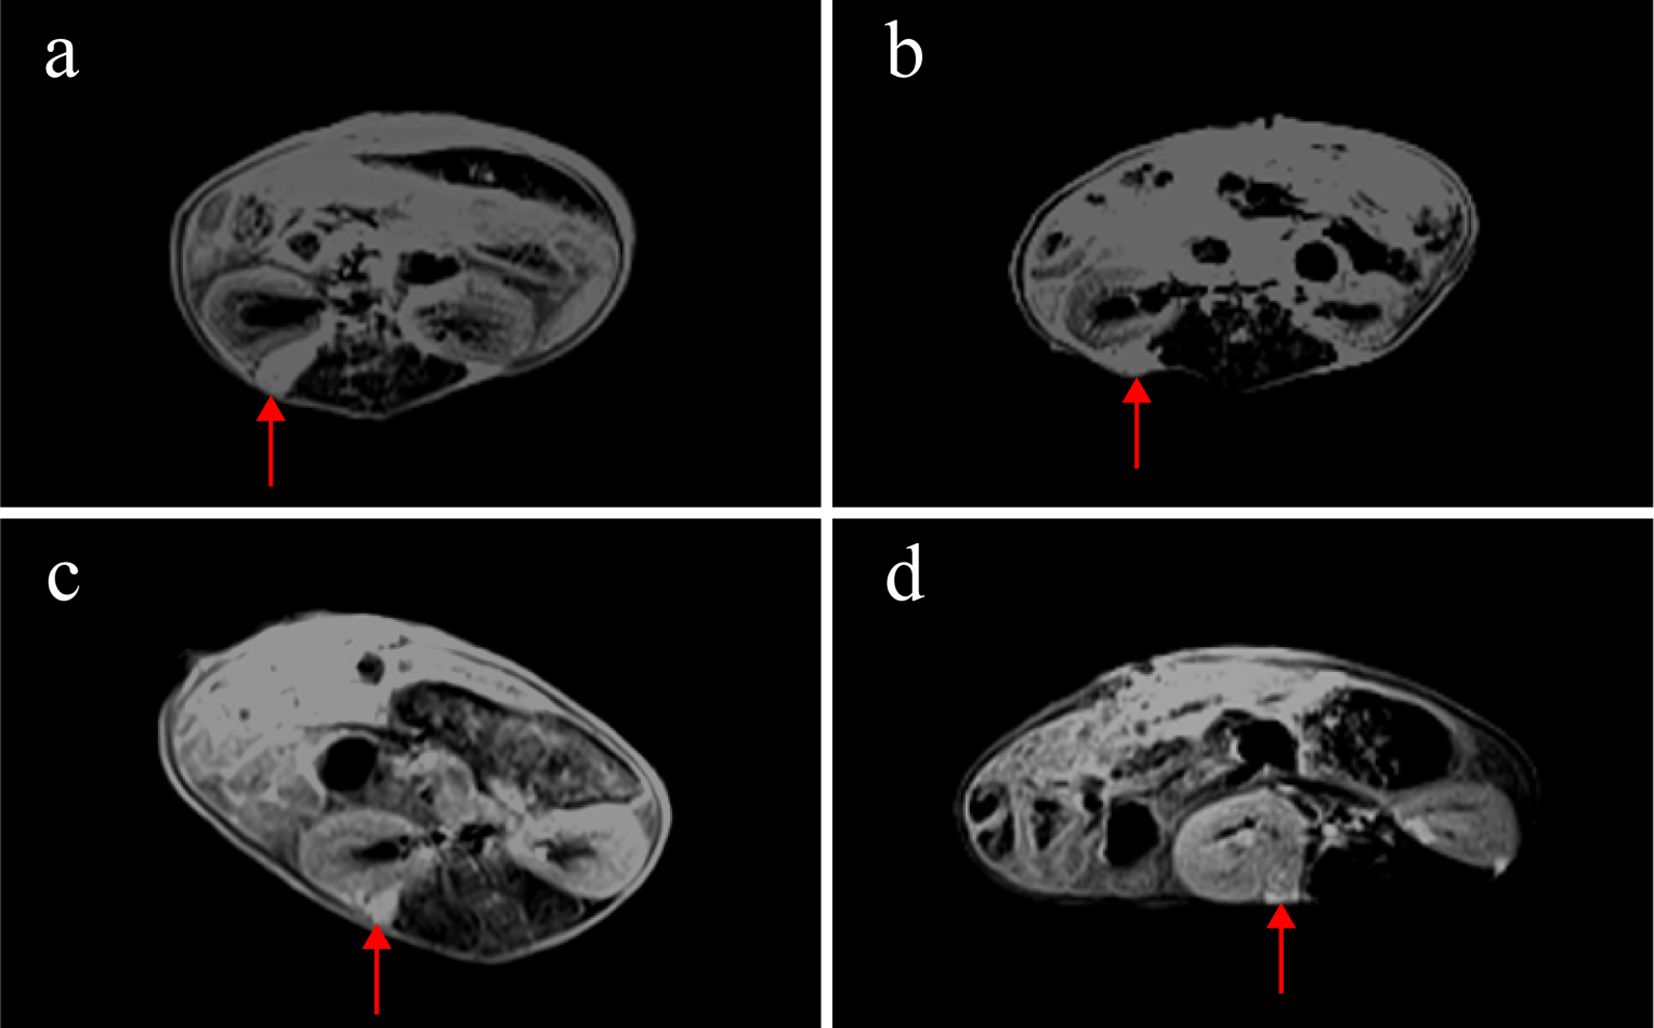

Weekly MRI observations were performed on the PDX. The tumor’s long and short diameters were measured using the software’s measurement tools. Serial observation of a PDX model revealed tumor growth dynamics, with measured long diameters of 2.5 mm, 2.1 mm, 2.0 mm, and 2.7 mm on days 8, 16, 25, and 32, respectively (Figure 2). The PDX tumor showed, Isointense and Hypointense on T1WI (Figure 3a), obvious Marked enhancement on T1WI contrast-enhanced(T1WI+C) scans (Figure 3b), Isointense and Hyperintense signal on T2WI (Figure 3c), companying with renal compression. When the tumor volume reached 100–500 mm³, the T2WI sequence was used to measure and calculate the tumor volume in the coronal (Figure 4a) and transverse (Figure 4b) planes. Subsequently, the mice were euthanized, and the tumors were excised (Figure 4c), Histopathological analysis diagnosed gastric adenocarcinoma (Figure 4d). The length and width of the tumors were measured using a vernier caliper, and the tumor volume was calculated. A comparison with the last MRI results showed no statistically significant difference between MRI and vernier caliper measurements of tumor volume: [(279.91 ± 78.94) vs. (277.10 ± 78.79), t = 1.41, P = 0.171] (Figure 4e).

Figure 2

MRI observations of a PDX model in renal capsule (arrow). (a) on the 8th day after establishment, the length of the tumor was 2.5mm, T1WI+C: (b) on the 16th day, the length of the tumor was 2.1mm, T1WI+C; (c) on the 25th day, the length of the tumor was 2.0mm, T1WI+C; (d) on the 32nd day, the length of the tumor was 2.7mm, T1WI+C; T1-weighted contrast-enhanced imaging (T1WI+C).

Figure 3

MRI findings of renal capsule PDX in T1WI, T1WI+C, and T2WI sequences(arrow). (a) Isointense and Hypointense on T1WI. (b) marked enhancement on T1WI contrast-enhanced(T1WI+C) scans. (c) Isointense and Hyperintense on T2WI, companying with renal compression. T1-weighted imaging (T1WI), T1-weighted contrast-enhanced imaging (T1WI+C), T2-weighted imaging (T2WI).

In PDX models, caliper measurements can be used to determine tumor size; however, this method proves challenging for gastric cancer PDX models in the renal capsule, typically requiring serial necropsies. Previous studies have found that among FDG-PET/CT, contrast-enhanced MRI and non-contrast MRI, non-contrast T2w MRI was the most effective and efficient imaging technique (32). Similarly, our study compared T2WI sequences with contrast-enhanced T1WI (T1WI+C) and found both modalities could clearly visualize renal capsule PDX. Notably, T2WI eliminated the need for contrast agent injection, thereby reducing examination time and avoiding potential trauma to mice from contrast administration. In this study, renal capsule PDX was first detected as early as day 8. On imaging, the PDX exhibited Hyperintense on T2WI and Hypointense intensity on T1WI compared to adjacent muscle tissue, with post-contrast marked enhancement indicating vascularization. These findings demonstrate MRI’s capability for early PDX detection. Consistent with prior research (33), our measurements from T2WI sequences showed no significant difference from caliper measurements, with pathological confirmation of gastric cancer PDX. Previous studies have demonstrated that PDX tumors maintain consistent histological characteristics compared to their original primary tumors (34–37). Our findings align with this observation, as the PDX models from F0 to F3 generations preserved the histological features of poorly differentiated adenocarcinoma. Notably, the number of Ki67-positive cells - reflecting cellular proliferative activity (38) - showed no significant differences across the F0-F3 generations.